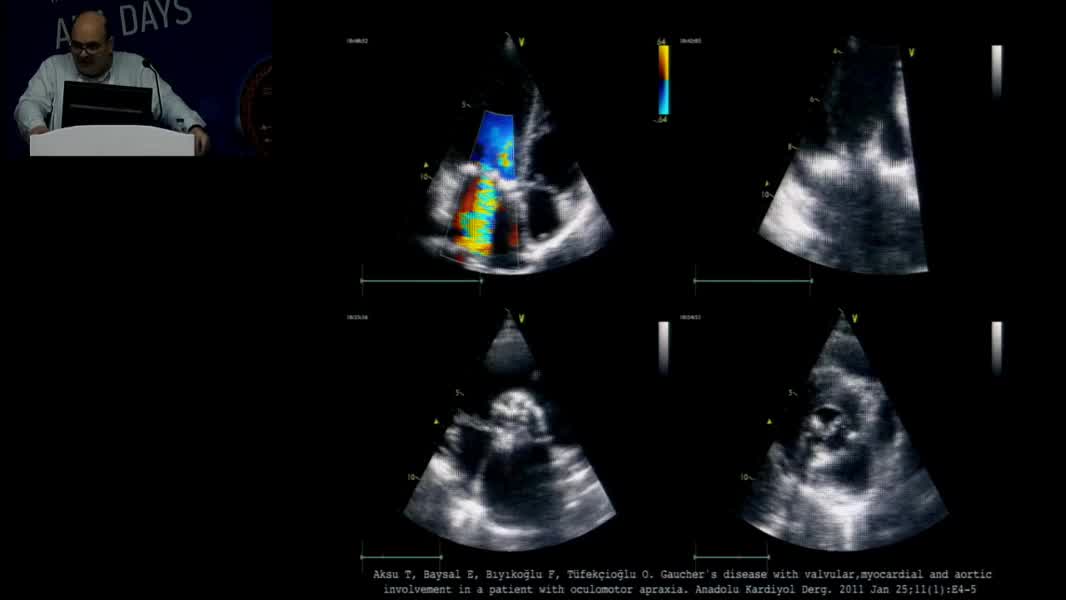

Echocardiographic Face Of Rare Cardiomyopathy And Fabry: Hands On Practical Echocardiography Course In The Diagnosis Of Fabry Disease And Cardiomyopathy Omaç Tüfekçioğlu (TR)

Nadir Miyokardiyopati ve Fabry’nin Ekokardiyografik Yüzü